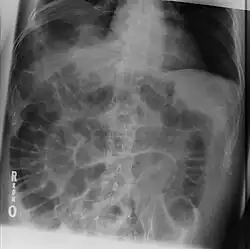

A radiologic sign is an objective indication of some medical fact (that is, a medical sign) that is detected by a physician during radiologic examination with medical imaging[1] (for example, via an X-ray, CT scan, MRI scan, or sonographic scan).

- Rigler's sign